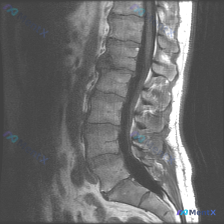

整理到一份影像资料,主诉考虑「脊柱侧弯」,但只放了一张矢状位腰椎MRI T1加权图像。 图像本身的客观表现大概是: - L1-L5椎体及骶骨轮廓清,高度大致正常,未见明显压缩骨折或滑脱 - 椎体骨髓信号中高,符合脂肪沉积,未见明确骨质破坏 - 椎间盘信号中等,椎间隙未见明显狭窄,硬膜囊前缘较完整 -...